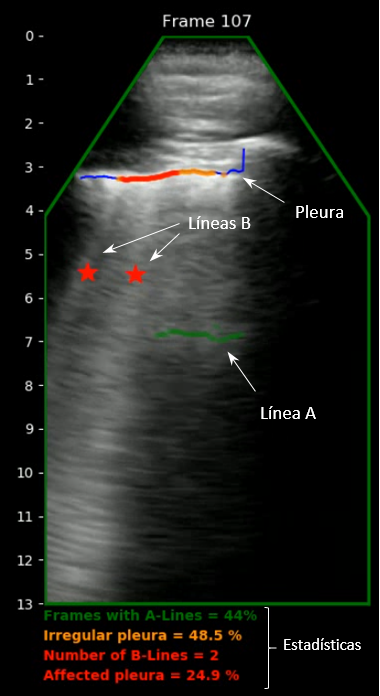

El dia 3 de marzo a las 11:00 hs presentamos los resultados de mas de 15 meses de desarrollo y pruebas clínicas del primer ecógrafo Pulmonar Inteligente Ultracov. Lugar: ITEFI CSIC C. Serrano, 144, 28006 Madrid Streaming : https://t.co/qvKVu8Lm8r

DASEL pyme madrileña radicada en Arganda del Rey, desarrollará, junto con el CSIC, la UCM y el H.U. La Paz el primer ecógrafo pulmonar 100% español orientado a la detección temprana y el seguimiento de la enfermedad #COVID19 La propuesta cuenta con la ayuda de CDTI.